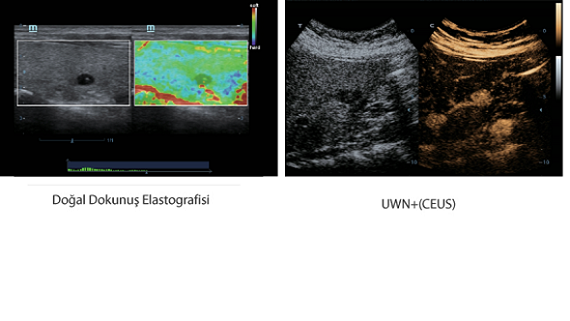

X-Insight, daha geli?mi? g?rĂŒntĂŒler elde etmek i?in kapsaml? bir ??zĂŒmdĂŒr.

Mindrayâin yeni ??zĂŒmĂŒ, geli?en en yeni ultrason teknolojileri ile birlikte, mĂŒ?terilerin g?rĂŒ?lerini klinik gerekliliklerle tam anlam?yla birle?tiren bir ??zĂŒmdĂŒr. Taptaze bir ruhla, gelece?e odaklanarak ve s?n?rs?zl???n pe?inde ko?arak, artan ?l?eklenebilirlikte sĂŒrekli olarak geli?en bir ??zĂŒmdĂŒr.

?ok y?nlĂŒ bir partner olarak, X-Insight'l? DC-60 Exp, her y?nĂŒyle gĂŒnlĂŒk klinik uygulamay? kolayl?kla ve belirsizlik olmadan y?netmenize yard?mc? olacak kapsaml? bir ??zĂŒm sunar.

MĂŒ?teri gereksinimlerine y?nelik g?rĂŒ?ler temelinde, X-Insight'l? DC-60 Exp, eXpress Clarity, eXceptional Intelligence ve eXceeding Experience ile gĂŒ?lendirilerek, hassas g?rĂŒntĂŒlemeyle yĂŒksek verimlilik sa?layacak ?ekilde tasarlanm??t?r.